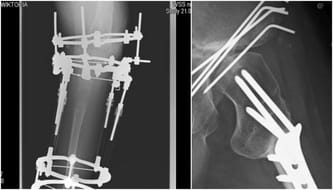

Operacje które miły mi pomóc, wydłużyć nogę i umożliwić chodzenie bez kul zniszczyły moje biodro, kolano i kostkę. Chciałabym znów zginać kolano, a co najważniejsze nie czuć bólu w każdej możliwej pozycji. Marzę o tym żeby całe cierpienie jakie przeżyłam w dzieciństwie, by być w pełni sprawną, dorosłą osobą, nie było zmarnowane.

Co 2 lata na pół roku zakładany chirurgicznie, przerażający aparat Llizarowa. 2 lata wycięte z życia z nogą w urządzeniu, które straszyło swym wyglądem. Skutek odwrotny od zamierzonego. Co prawda nogę mam dzisiaj dłuższą, ale oberwało kolano. Staw po prostu nie wytrzymał takiej siły i gdy miałam 13 lat, zmuszona byłam przejść operację, ale proces był już nie do zahamowania. Każdy zabieg daje nadzieje, które im dłużej dojrzewają w człowieku, tym trudniej pogodzić się z tym, że nigdy się nie urzeczywistnią. Posypało się biodro. Ostatni staw, który w mojej nodze funkcjonował jako tako.

Do 14 roku życia poruszałam się o dwóch kulach. Koszmar! Wiecznie odciśnięte dłonie, bezradność w autobusie, upadające kule w sklepie podczas płacenia, odbierania telefonu. Gdybym miała pewność, że to na pewien czas, na chwilę. Ale nie miałam. Lekarze w kraju podjęli decyzje. Zniszczone kolano ze zwyrodnieniami 80-letniej osoby, wymaga endoprotezy – sztucznego stawu. Sztuczne kolano to jednak ryzyko, wielka niewiadoma i nauka chodzenia od nowa. Jaką mam pewność, że moja noga, która nie ma nawet kości strzałkowej, przyjmie protezę, przetrwa rehabilitację?